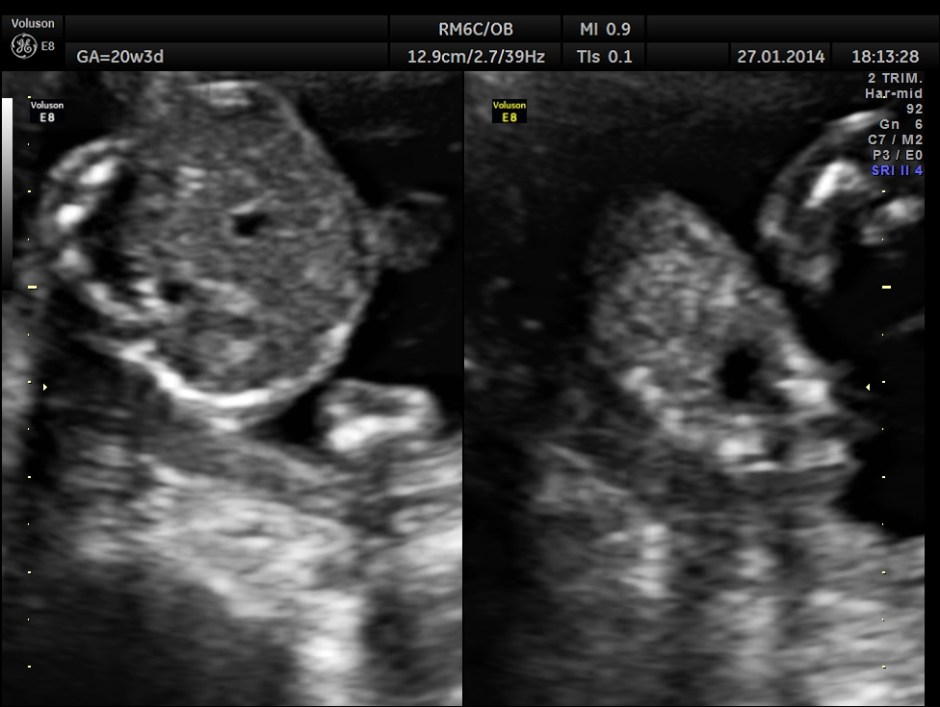

As it can be seen , the GA was around 20 weeks , but the AUA was around 17 weeks. All parameters – BPD, HC, AC, FL are < 2.3 %tile and all other long bones are < 5.0 %tile.

The kidneys and the urinary bladder appear to be normal.

Amniotic fluid appears to be adequate.